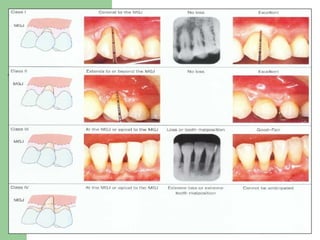

CONSIDERAR Diagnostico y control del factor etiológico. Tipo de recesión (Clase de Miller). Biotipo gingival.

CONSIDERAR Diagnostico ycontrol del factor etiológico. Tipo de recesión (Clase de Miller). Biotipo gingival.

II. TAMAÑO DEL DEFECTO    Miller I y II  - Superficial < 3 mm - Moderada 3- 4 mm - Lesiones ≥ 5 mm  PRONÓSTICO INCIERTO Miller III:   MAL PRONÓSTICO Recubrimiento Completo FACTORES QUE INFLUENCIAN LOS RESULTADOS  QUIRÚRGICOS

II. TAMAÑO DELDEFECTO   Miller I y II - Superficial < 3 mm - Moderada 3- 4 mm - Lesiones ≥ 5 mm PRONÓSTICO INCIERTO Miller III: MAL PRONÓSTICO Recubrimiento Completo FACTORES QUE INFLUENCIAN LOS RESULTADOS QUIRÚRGICOS